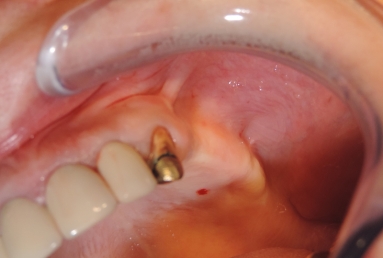

Initial situation: The patient needs dental implants on the left side of the maxillary jaw in order to have a fixed prosthetic restoration. But the bone is insufficient vertically and laterally, because the extractions were made a long time ago, which caused the extreme bone resorption and the vertical migration of the sinus floor.

Final situation: an external sinus lifting procedure was performed. The sinus membrane was lifted off the sinus walls and new bone was applied in the vertical space created ( Bio Oss- switzerland- bovine origin). After 6 months, while the new bone is integrated in the maxillary bone of the patient, dental implants can be applied. the case is still during treatment.